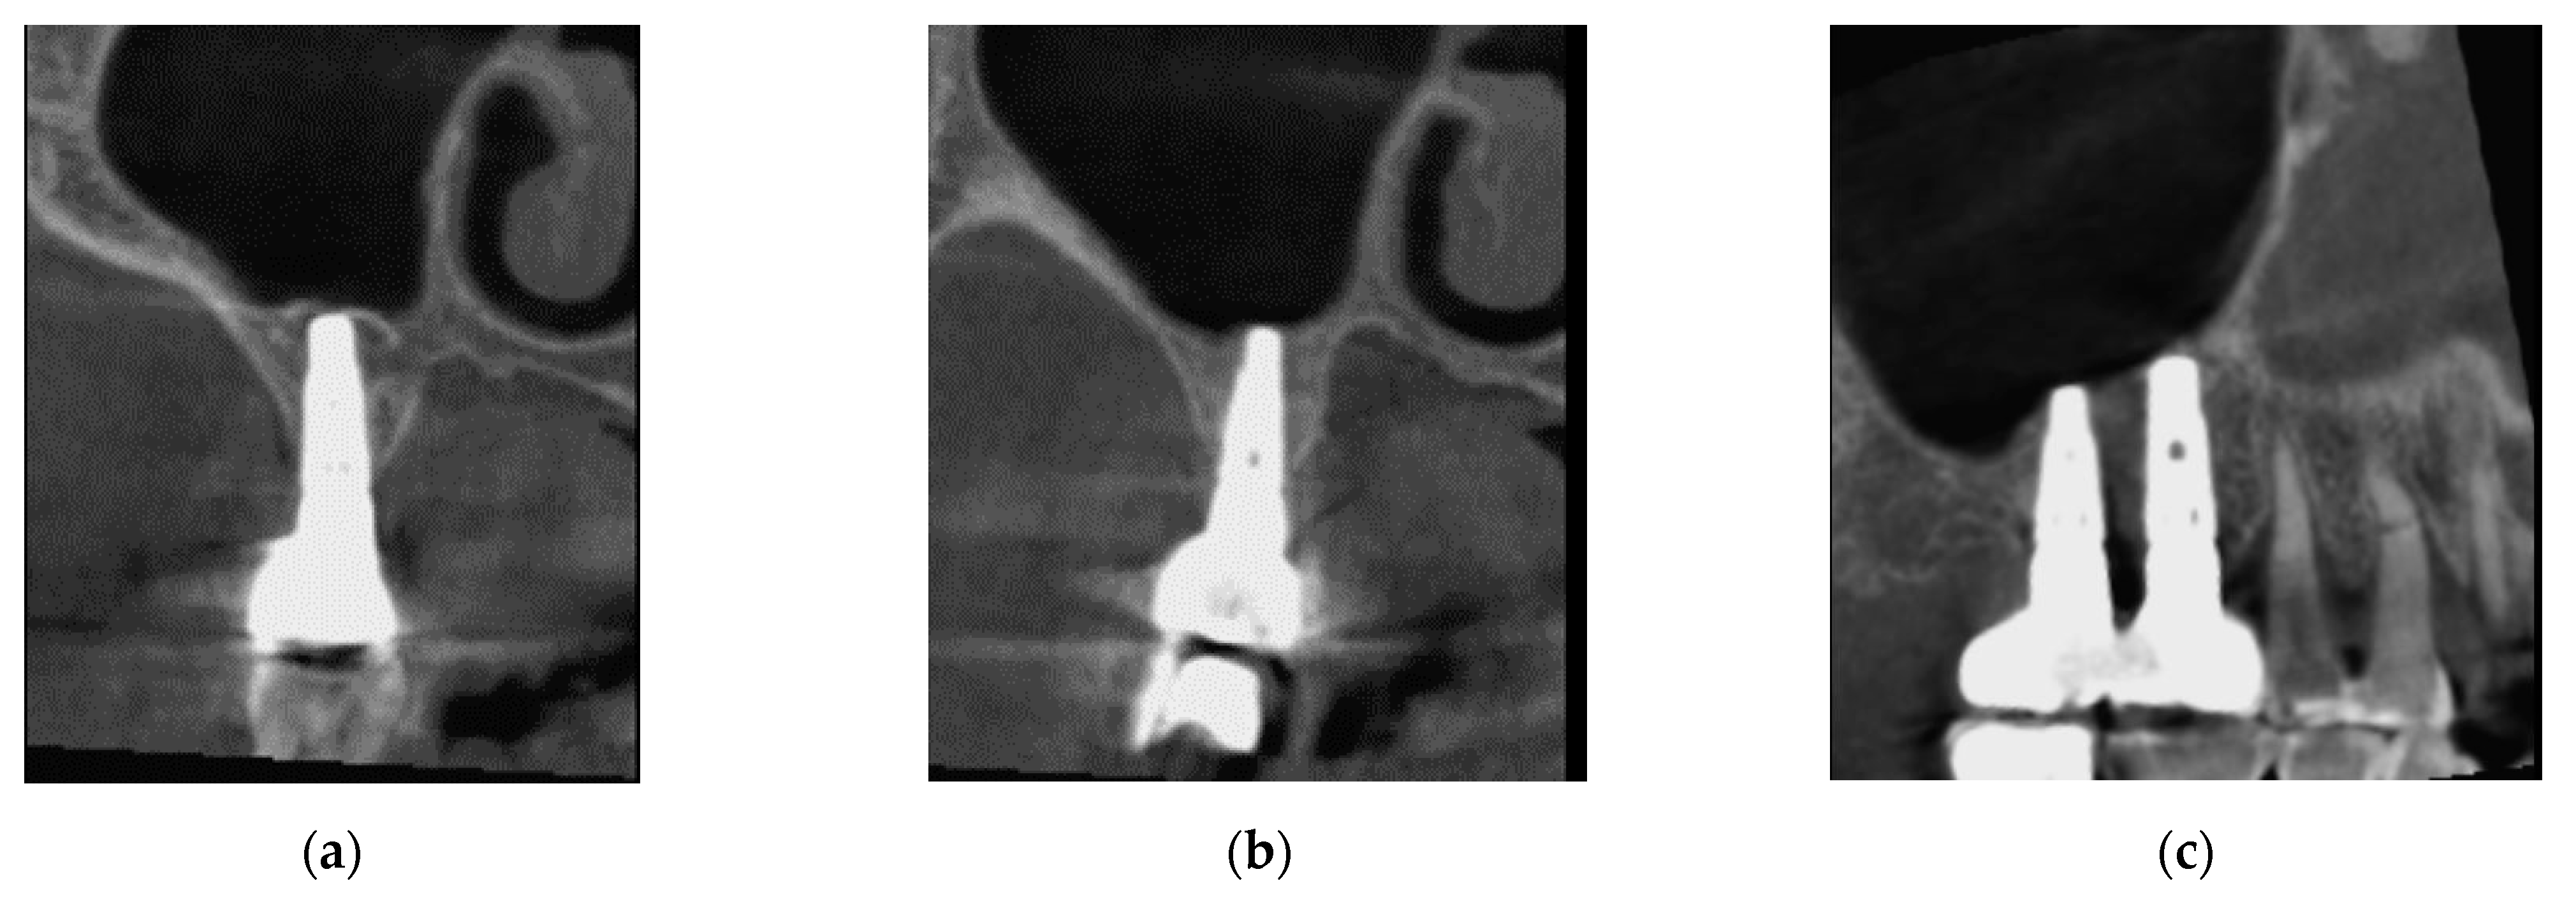

3.2. Patient Two

3.2.1. Surgery

3.2.2. Follow Up